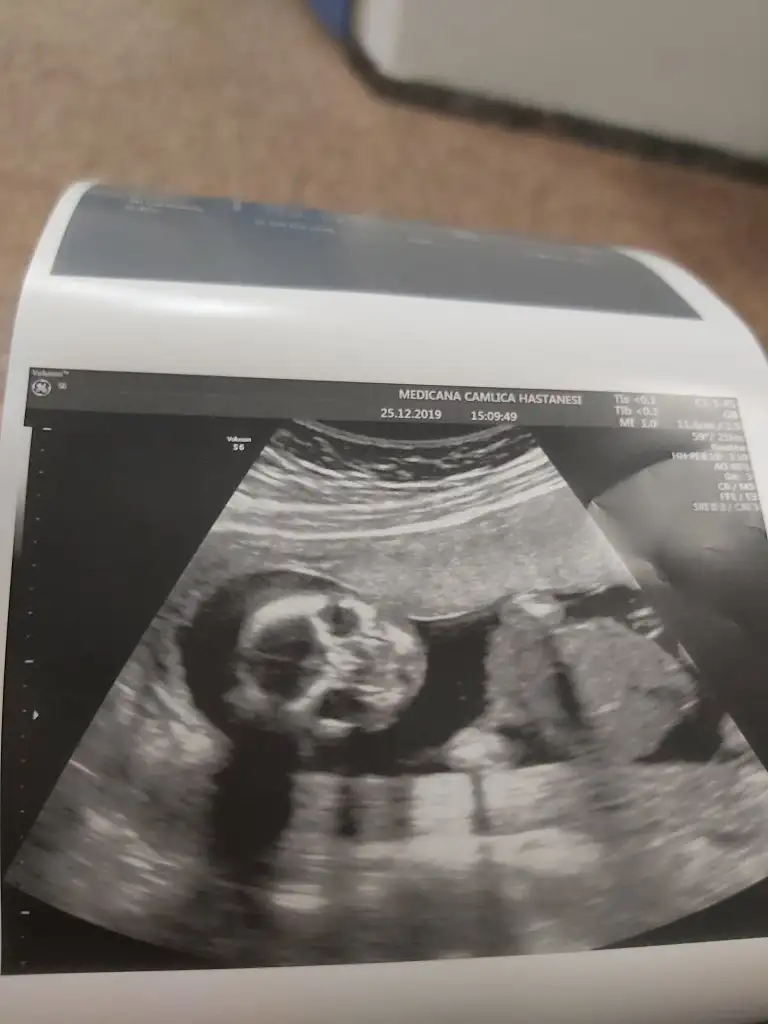

dr soylemeden siz gorun genital nub teorisi ( bebegin cinsiyeti)

ya kızlar bu resim bnim kaç gündür aklımı karstryo burda kız gibi doktor erkek dedi